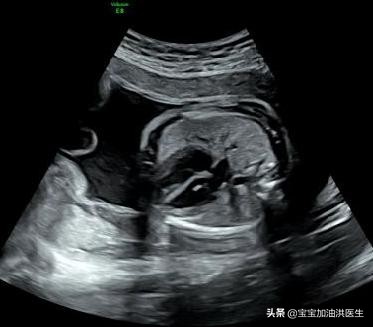

胎儿心室强光点,强光斑,医生在超声报告中可能会描述为心室内强回声光斑或心内灶性强回声。多数只有一处,也可多发,心脏的左室最多见。产生可能与乳头肌腱索炎症、增厚、钙化有关,本身无碍健康和心脏功能,属于一种影像上的“不同”。

胎儿心室内强光斑是一个声像图表现,而不能说是一种心脏畸形;大概会有2-3%左右的胎儿检查时可能会发现这个情况存在。